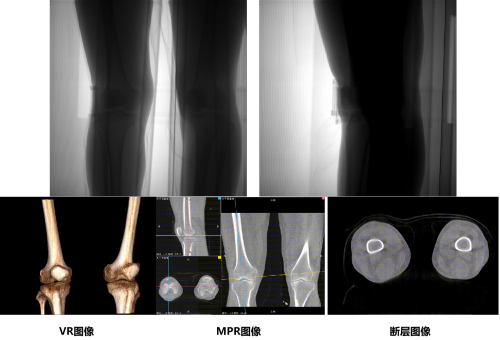

通过安健科技CBCT-DR 珠穆可以完成负重位状态下的三维扫描与重建,能够更丰富的呈现受检者膝关节受力改变状态,可完成断层图像重建、MPR多平面重建以及VR体绘制,给临床提供更多的影像学信息;同时相较于普通平片下的负重位拍摄,负重位动态三维影像重建技术能够避免二维状态下的组织结构重叠、密度分辨率不足、组织解剖结构难以分辨等问题,极大的降低了二维负重位检查带来的漏诊率。